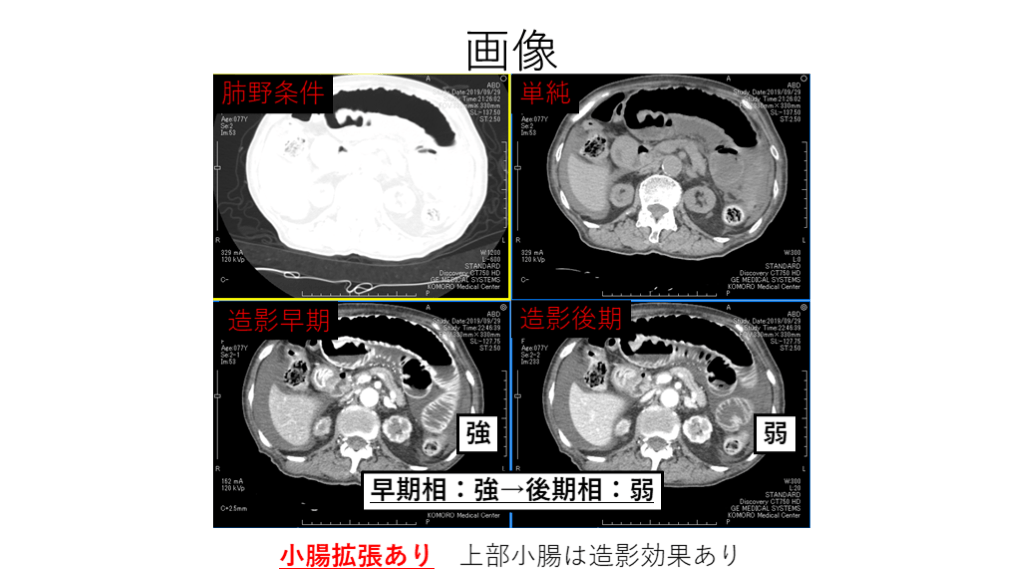

画像 小腸拡張あり 上部小腸は造影効果あり 肺野条件 造影後期 造影早期 単純 強 弱 早期相:強→後期相:弱

#8.